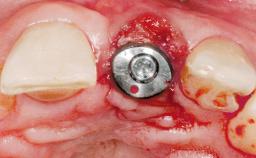

Immediate Flapless Placement of an Implant in a Maxillary Right Lateral Incisor Site

This 43-year-old male patient, a non-smoker, came to our practice because of a fracture of tooth 12 caused by a bicycle accident. Due to the combined para- and infrabony crown and root fracture, tooth extraction, and subsequent implant placement were suggested to the patient as the therapy of choice. The patient had high esthetic expectations with regard to the treatment outcome and asked for an immediate fixed provisional restoration. His individual esthetic risk profile summed up to a medium esthetic risk.

Placement Protocol Immediate implant placement

Socket Morphology Single-root socket

Socket Integrity Sufficient, with intact bone walls